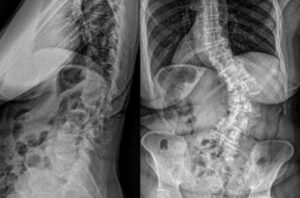

Dr. Jay Turner performs T10-pelvis fixation utilizing 4 iFuse Bedrock Granite® implants to provide multiple points of fixation to the pelvis.